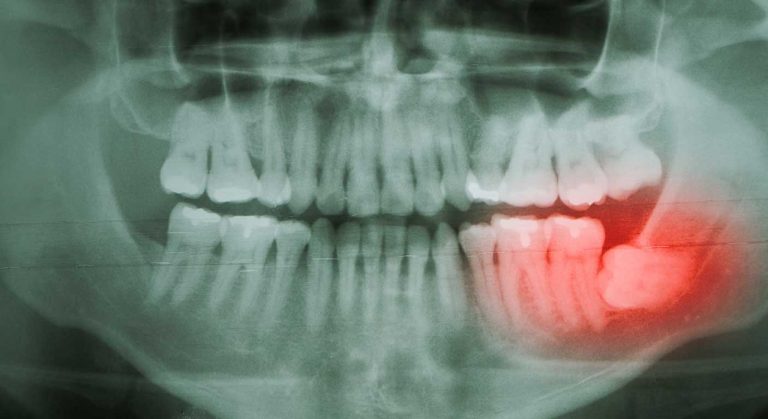

- دندان عفونی: اگر لثههای کودک شما فقط در نزدیکی یک یا دو دندان متورم است و دندان او نیز حساس است یا دنداندرد دارد، این میتواند نشانه عفونت دندان باشد. عفونت دندان در داخل دندان و بین دندان و لثه میتواند باعث تورم لثه شود. این واکنش طبیعی بدن است و زمانی اتفاق میافتد که تعداد زیادی باکتری وجود دارد. یکدندان عفونی مشکلی بسیار جدی است که بهصورت طبیعی رخ نمیدهد. در صورت درماننشدن، دندان میمیرد و نیاز به کشیدن دارد و عفونت میتواند در این فاصله گسترش یابد. اگر به دندان عفونی مشکوک هستید، دراسرعوقت با دندانپزشکی تماس گرفته و نوبت اورژانسی دریافت کنید.